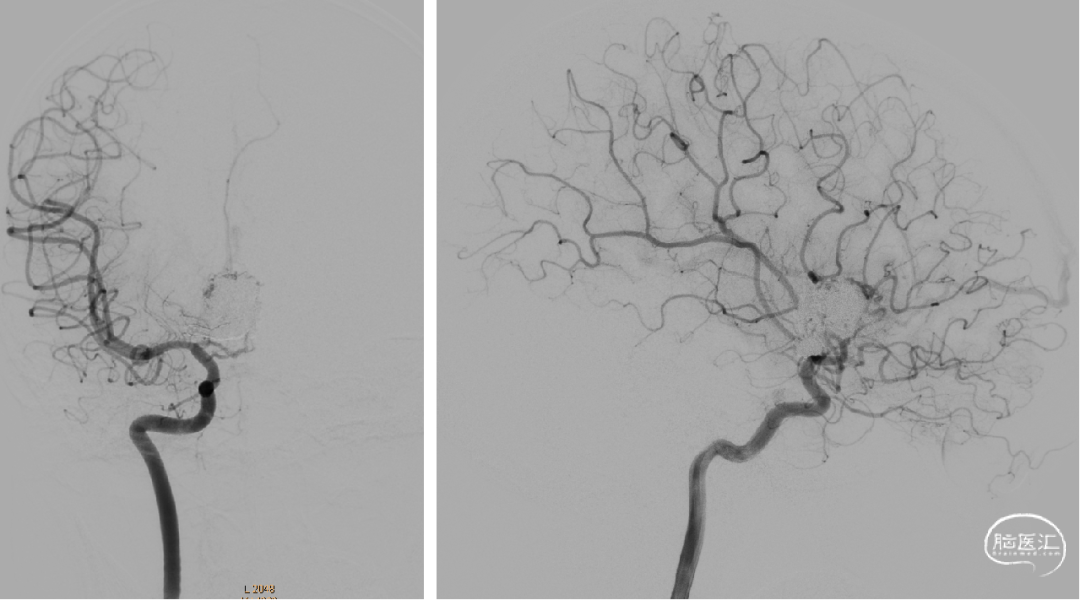

7个月前第一次静脉入路栓塞

术后即刻造影

术前检查